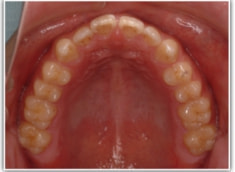

開咬(かいこう:オープンバイト)ケース

治療法:表の矯正(T21ブラケット)

(インプラントアンカーや外科矯正は行わず、エラスティックと機能訓練のみ)

治療前